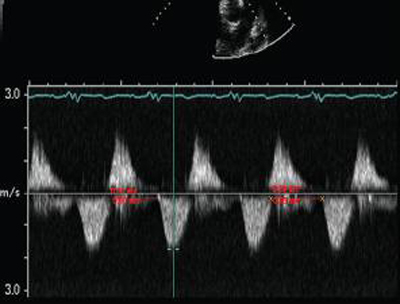

Doppler in a patient with pulmonary regurgitation following repair of tetralogy of Fallot. The patient has a restrictive right ventricle, and Doppler shows evidence of restriction with an antegrade ‘A’ wave in the pulmonary artery

From: Chaturvedi RR, Redington AN. Heart. 2007 Jul;93(7):880-9; used with permission